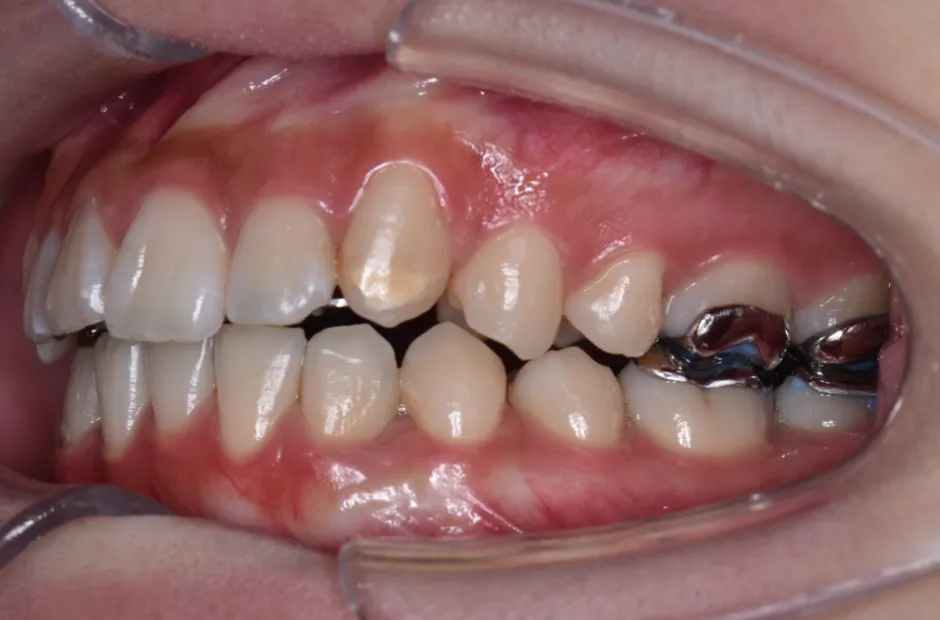

叢生

| 診断名・主訴 | 叢生 |

|---|---|

| 年齢・性別 | 43歳・女性 |

| 治療期間・回数 | 2年7か月 27回 |

| 治療に用いた主な装置 | 舌側矯正 |

| 抜歯部位 | 両顎4,4 |

| 治療費 | 100万円(税抜) |

| リスク・副作用 | 装置による違和感・疼痛・歯肉退縮・歯根吸収・虫歯のリスクなど |